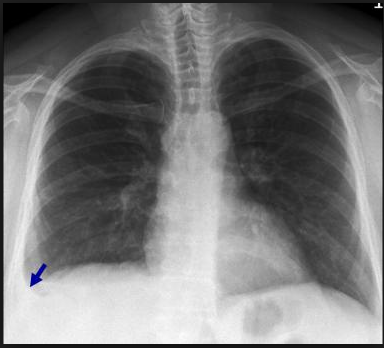

溶骨所見:下写真の矢印部位。胸部レントゲンで一緒に写る上腕骨で溶骨所見が見られることもある。溶骨性の骨転移がうつりこんでることがあるのでよくチェック。

骨折はないか:肋骨をひとつひとつ見ていく。黒矢印のところで肋骨骨折が見られる。